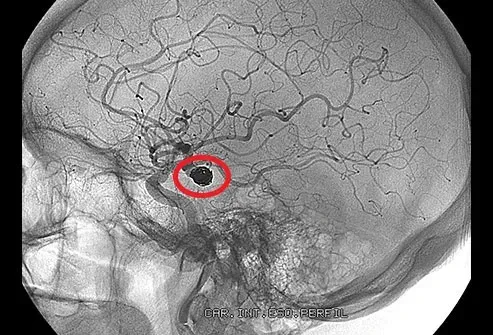

Umístění: mozek

Tlak se staví, když krev nemůže protékat normálně. Těžká blokování někdy může vést k mrtvici. Bez kyslíku z krve začnou vaše mozkové buňky zemřít během několika minut. Sraženina v mozku může způsobit bolesti hlavy zabavení problémů s řeči a slabostí někdy na jedné straně těla.